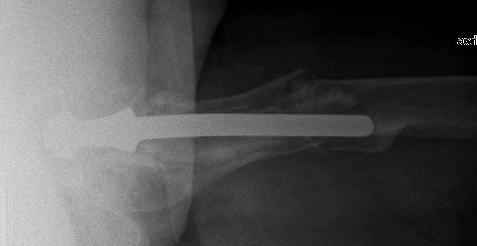

You transformed a cemented hip prosthesis to a cementless revision hip prosthesis with a little approach.

* your nail has a point of minus resistance at the tip of femural stem and at the fulcrum of the fracture; by the time could it break?

* by the time stem and nail could reciprocally move?

* distal fixation of the nail is based near only on two screws : are they sufficient to secure a good stability before fracture consolidation?

* materials of the stem and nail (I think Iron steel in both); if they should be different (and many hip prosthesis are made by an alloy that is not the same of the nails) we could see electrolytic phenomena

I generally should prefer a long stem revision prosthesis, as that allegated.